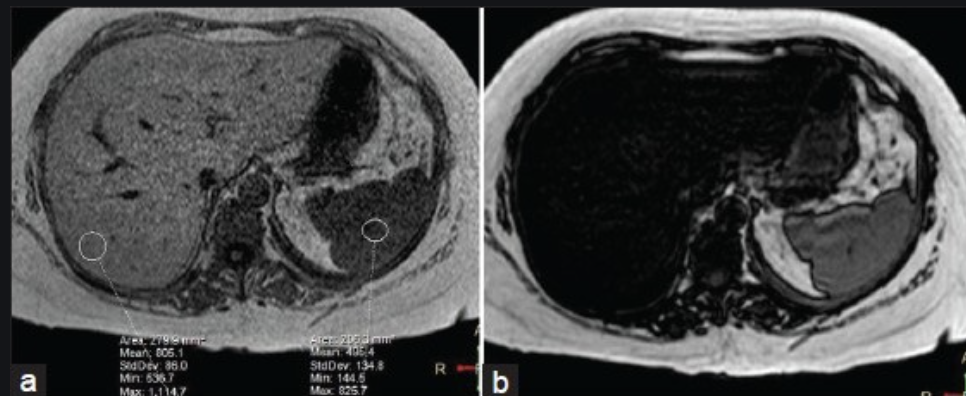

Ix: How MR in/out works.

Ix: when water & fat protons are in the same MR voxel the fat/water signals are summed in in-phase, subtracted in out-of-phase.